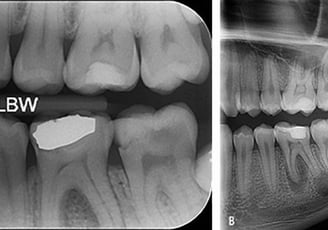

Radiografii intraorale

Aceste radiografii sunt realizate cu senzori intraorali și oferă imagini detaliate ale unor zone specifice ale gurii, precum un singur dinte sau rădăcinile acestuia.